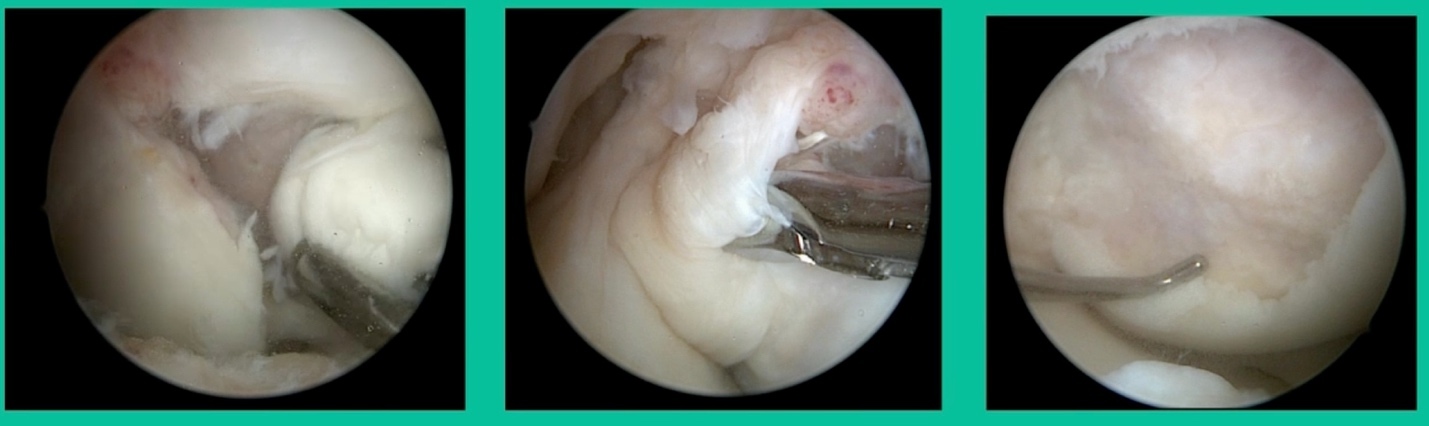

I thought I might be able to fix it. I had the conversation with the family, get in there, started taking it apart with a Vanguard elevator grasper. Behold, it’s really just cartilage fragments (Figure 2).

There’s two or three of them. We debrided it. It felt normal in six weeks, no complaints in three years. What are the results of juvenile debridement? They’re actually profoundly good. You would never expect this in the scheme of things, but the natural history of removing the piece is actually very good in the juvenile patient. However, once again, fix it if you can. Debride it, if you can’t. If they get symptoms, we restore it, and then never leave unstable fragments.

You look at this one, you say, “what are you going to see when you get in there?” This is one when you get in there, you say, I’m not even sure I’m in the right knee because you almost don’t see it. That happens in patients who were painful, but they don’t look macroscopically unstable. Pediatric orthopedic surgeons tend to drill these. These are the ones that I see as failures. I think when you’re talking about something that’s mechanically unstable, it’s hard to understand why drilling would actually make it work without fixation. Even if it’s microscopically unstable.

The challenge is this. This series of patients were populated by early decisions to treat when patients don’t have symptoms. That’s a problem in my mind. Post-Op, they protect their weight-bearing. That’s actually treatment. These are often smaller lesions of the medial femoral condyle. They do really well. That being said, it’s an option. It’s not my option. My option for someone who’s macroscopically unstable is we use biocomposite screws (Figure 4).

These biocomposite screws will hang around for upwards of a year. So, they’re not innocuous, and you’ve got to bury their heads. But we drill it, we tap it, and we stabilize it, and then we drill from the side in an effort to promote further biology. This is analogous to just arthroscopic fixation, but I don’t go back, and I don’t remove the screws. Then I’ll typically take a K-wire from the side after I place these screws. I keep them non-weight-bearing for eight weeks. I don’t remove it. I wait four months before they go back to high-impact activities like this patient did here.

What are the outcomes? Very, very favorable. We had 87% survivorship using a biocomposite screw. Would I use it for a macroscopically unstable one? I wouldn’t. I would tell you that the biomechanics are not nearly as good, and it is not innocuous. If you leave the head proud, this will scratch the tibia and cause a railroad track there. You must bury them, but don’t take them out.